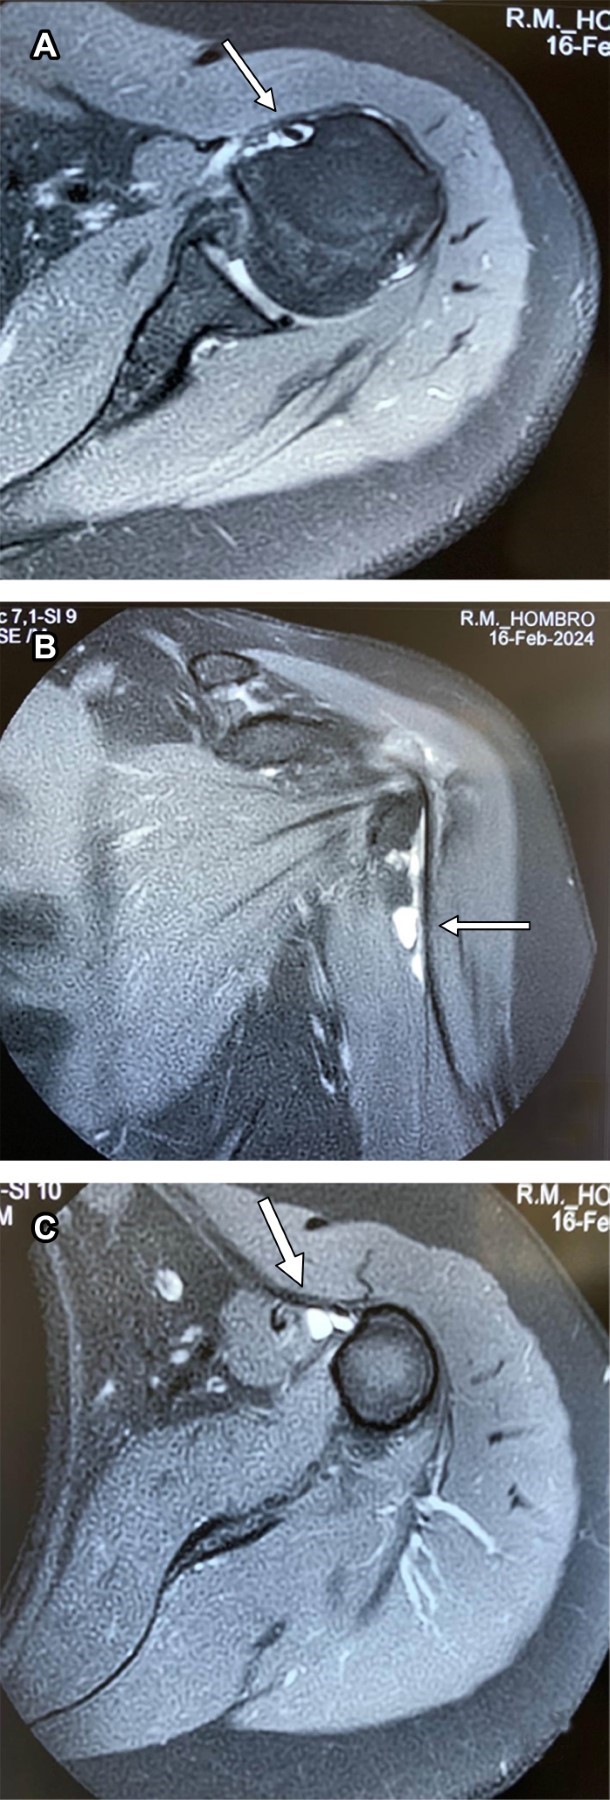

Se trata de paciente femenino de 69 con dolor en el hombro izquierdo de seis meses de evolución, principalmente con movimientos de abducción y flexión de codo. A la exploración de hombro izquierdo: arcos de movimiento limitados en abducción a 90° por dolor al igual que rotación externa de 45°, a la palpación masa dolorosa de aproximadamente 2 cm en borde interno del tendón de la porción larga del bíceps por debajo de la corredera bicipital. Prueba de choque de Neer, Hawkins y prueba de Yergason positivas; pruebas de inestabilidad de la articulación glenohumeral negativas. Las radiografías simples no mostraron hallazgos anormales. La resonancia magnética mostró: tendinosis del supraespinoso con ruptura parcial en su inserción, además de acromion tipo III con osteofitos subacromiales causantes de pinzamiento (Figura 1); en ponderación T2 se encontró tendinopatía de la porción larga del bíceps braquial con incremento de líquido en la corredera bicipital y quiste sinovial en su tercio proximal de 2.0 × 1.4 × 1.2 cm, con apariencia de estar encapsulada por la vaina del tendón bicipital (Figuras 2 y 3). Se canalizó a cirugía articular.

Figura 1